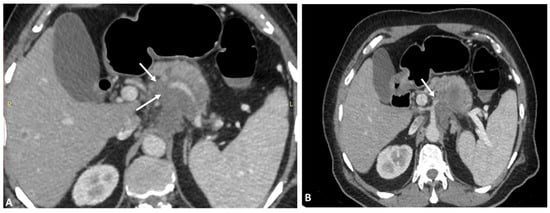

3.1. Variations of Common Hepatic Artery

3.2. Variations of Right Hepatic Artery

3.3. Variations of Left Hepatic Artery

4. Detection of Hepatic Artery Variations and Their Classifications